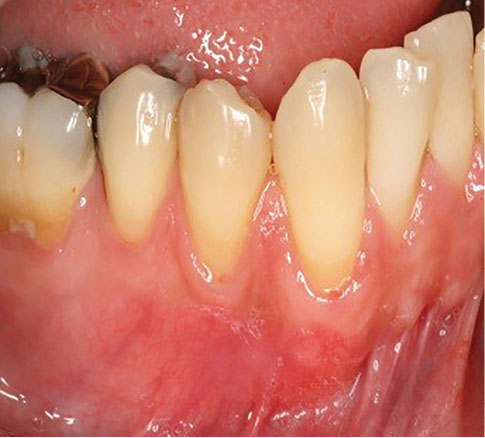

The sulcular incision was made at the recipient site. The flap was beveled in the interdental papilla region adjacent to the tooth with the exposed root. A partial-thickness flap was raised beyond the mucogingival junction. The mesiodistal width of the incision was extended to the line angle of the adjacent teeth mesially and distally. Mesial and distal vertical releasing incisions were also made. The required graft width was measured using a periodontal probe. A connective tissue graft was prepared from the palate, measuring 1–1.5 mm in thickness and fixed at the recipient site with a 4-0 bio-absorbable polyglycolic suture. Then, a coronally repositioned flap was relocated to cover the graft and stabilized in the site with a sling suture (Figures 1 and 2). A 10×20-mm and 0.6–0.9-mm-thick graft was prepared from acellular dermal matrix graft [Cenoderm, Tissue Regeneration Corporation (TRC), Iran] (Figure 3) according to the manufacturer’s instructions. The graft was placed at the recipient site from its porous surface from the CEJ to 2–3 mm beyond the bony margin of dehiscence and fixed at the recipient site with a 4-0 bio-absorbable polyglycolic suture. Then, a coronally repositioned flap was relocated to cover the graft and stabilized with a sling suture (Figures 4 and 5).

Figure 4.

Cenoderm site before surgery.